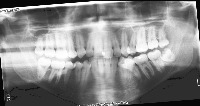

downloadClasses (32)

tooth_11

tooth_12

tooth_13

tooth_14

tooth_15

tooth_16

tooth_17

tooth_18

tooth_21

tooth_22

tooth_23

tooth_24

tooth_25

tooth_26

tooth_27

tooth_28

tooth_31

tooth_32

tooth_33

tooth_34

tooth_35

tooth_36

tooth_37

tooth_38

tooth_41

tooth_42

tooth_43

tooth_44

tooth_45

tooth_46

tooth_47

tooth_48